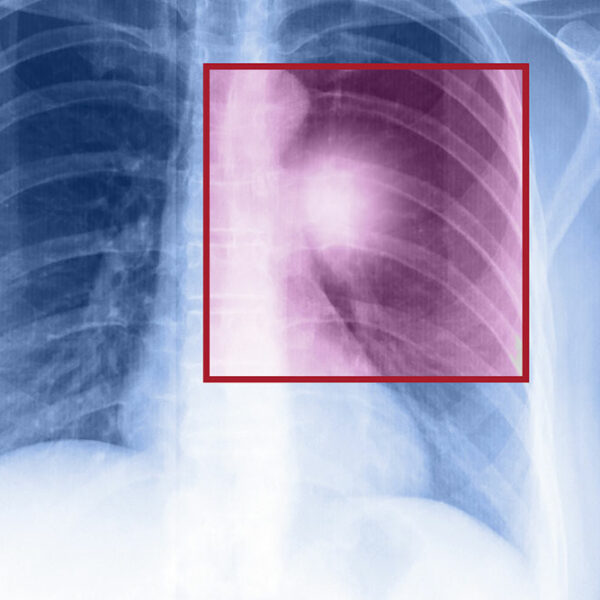

- Chest X-ray which provides detailed images of the lungs.